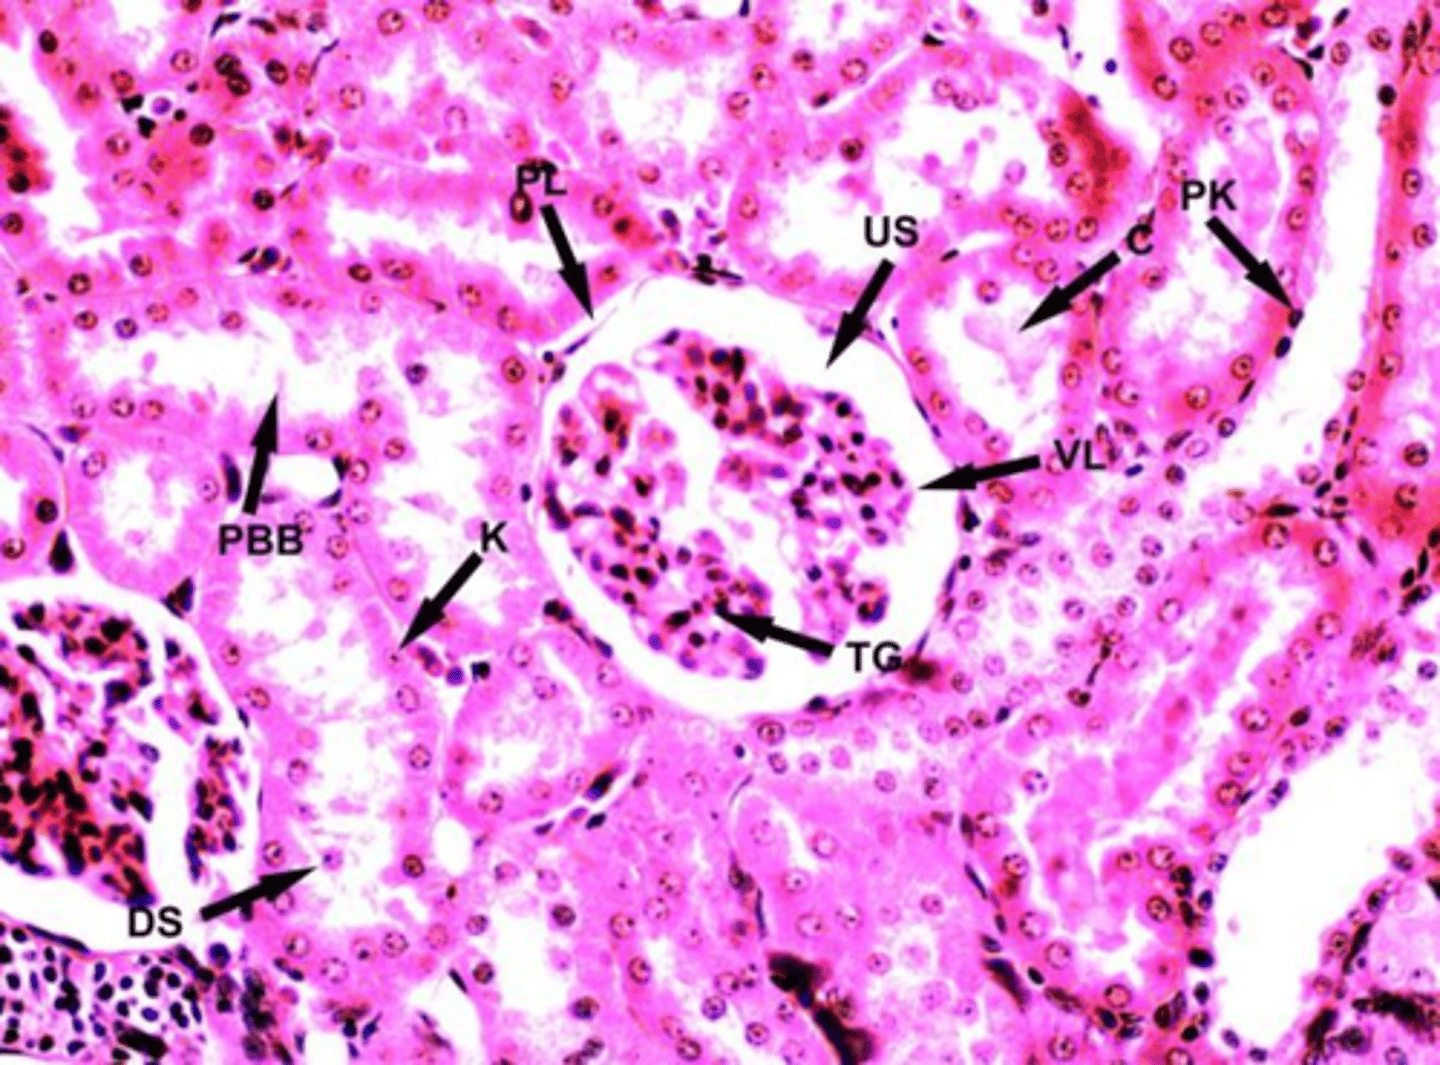

kidney nephron

glomerulus, tubules, glomerular capsule

ingredients of kidney nephron